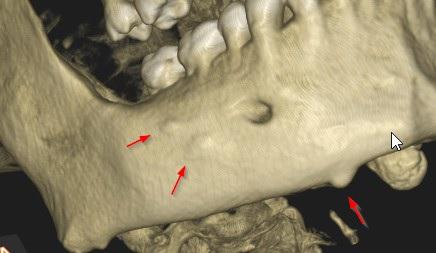

Pacjentka: wiek 34 l.

Badanie z dnia: 05.08.2023

Dane kliniczne: diag. guzów w obrębie części twarzowej czaszki -

okolica z.36 oraz kąta lewego żuchwy - w wywiadzie fibromatoza

Na podstawie obrazu radiologicznego w obrębie twarzoczaszki ukazującego liczne kostniaki, zębiaki, zaburzenia rozwojowe zębów: zęby nadliczbowe, zęby zatrzymane, mikrodoncja, zwapnienia w obrębie nosogardzieli stwierdza się jako zasadne przeprowadzenie diagnostyki w kierunku zespołu Gardnera.